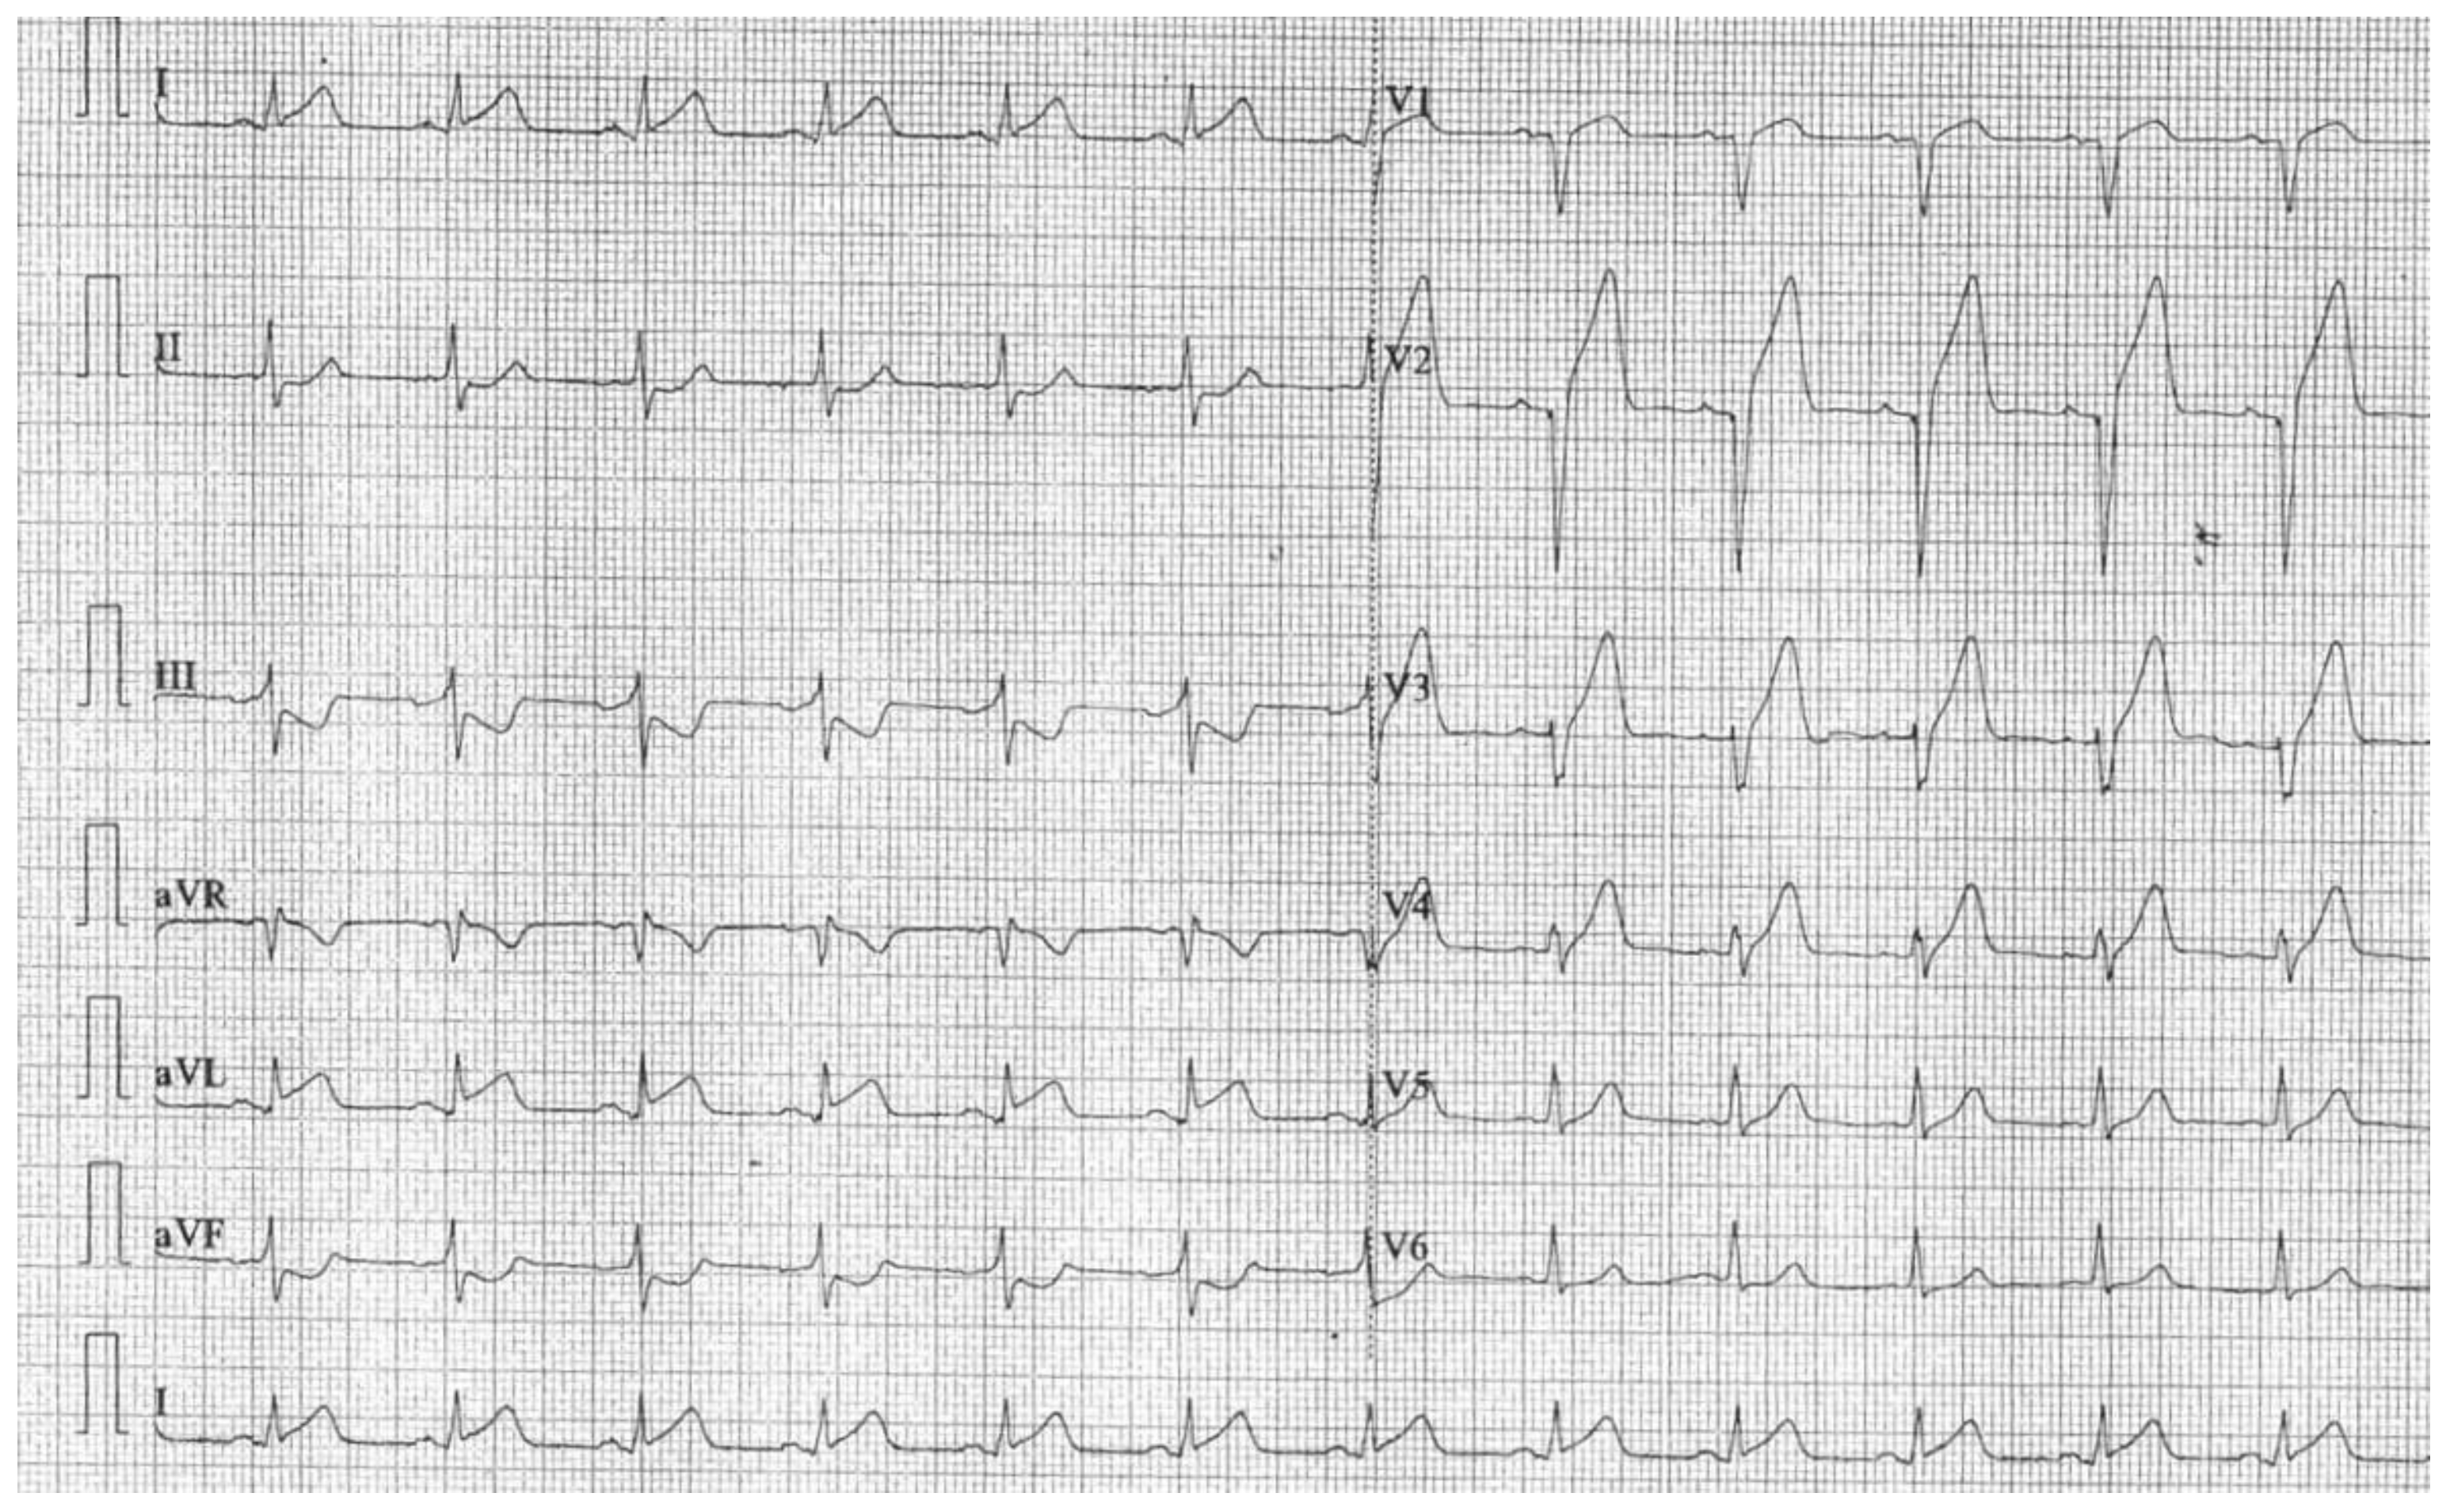

2. Detailed Case Description